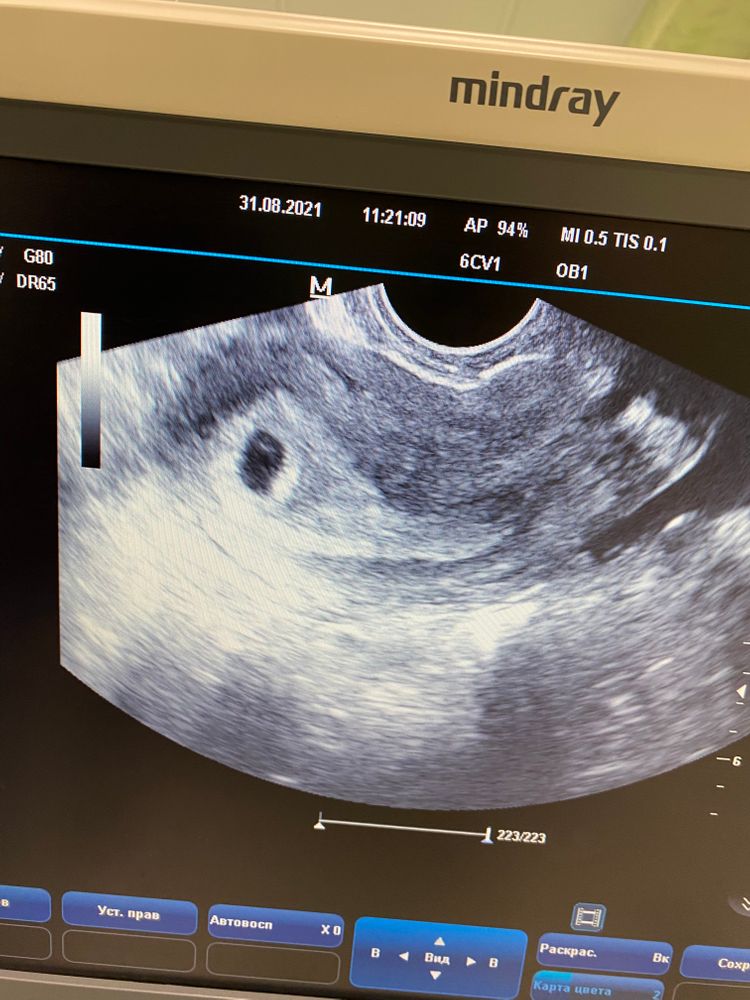

В 5 только пя, в 5. 3 жм появился, в 6. 1 эмбриончик показался. А страшилок на каждый срок хватает 🙈не читаю такое